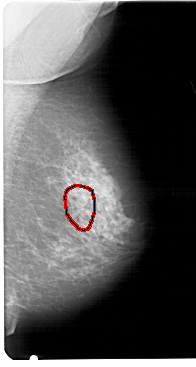

RIGHT_MLO LINES 5491 PIXELS_PER_LINE 2926 BITS_PER_PIXEL 12 RESOLUTION 43.5 OVERLAY

FILE: A_1458_1.RIGHT_MLO.OVERLAY

TOTAL_ABNORMALITIES 1

ABNORMALITY 1

LESION_TYPE CALCIFICATION TYPE PLEOMORPHIC DISTRIBUTION CLUSTERED

ASSESSMENT 4

SUBTLETY 3

PATHOLOGY BENIGN

TOTAL_OUTLINES 1

BOUNDARY